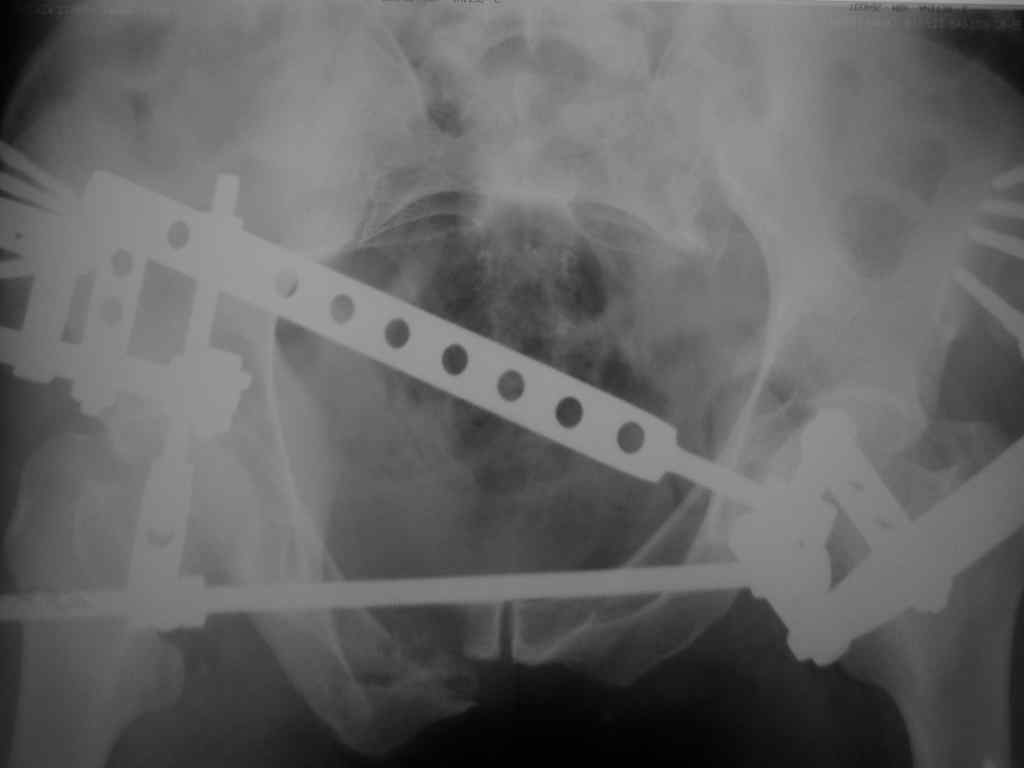

Еще снимок